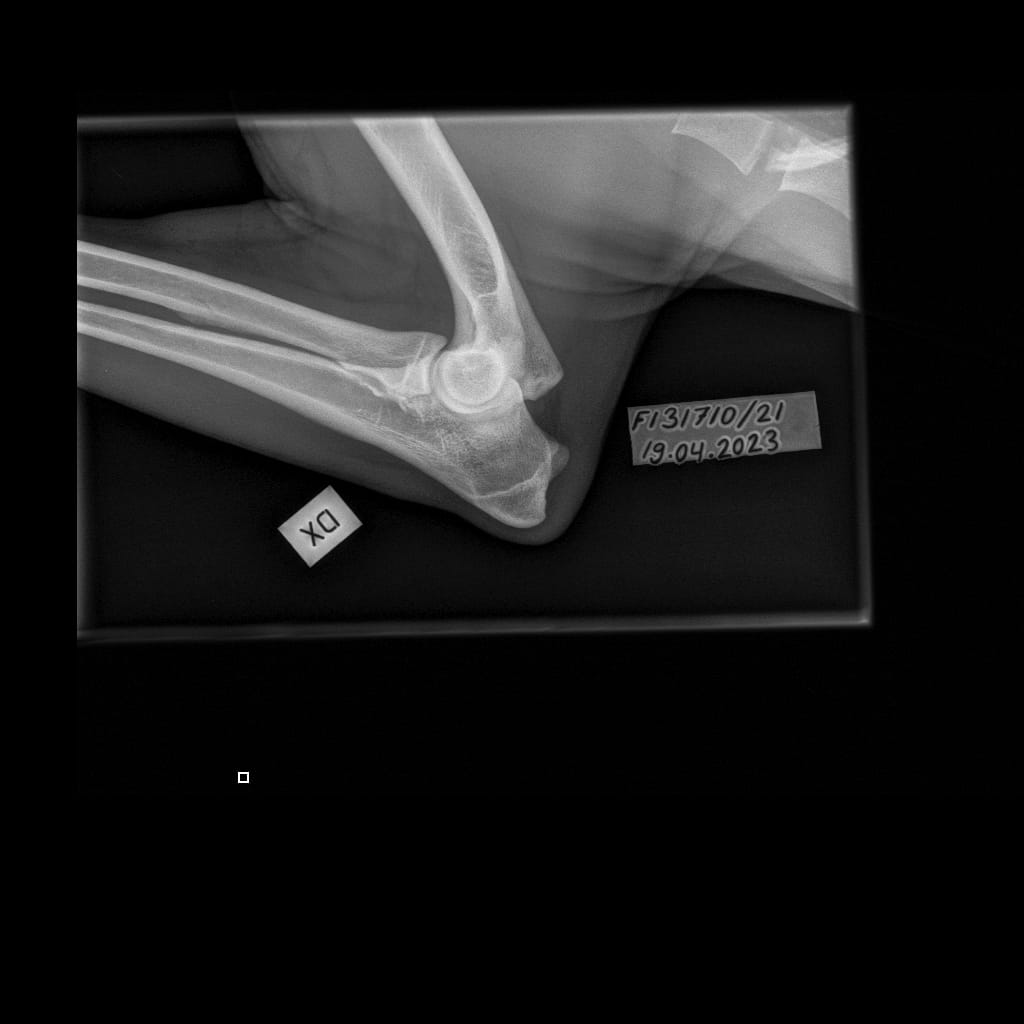

Topi’s OCD

Eturaajat -Kyynärnivel LAT-6.11.2023-16_02_19-577